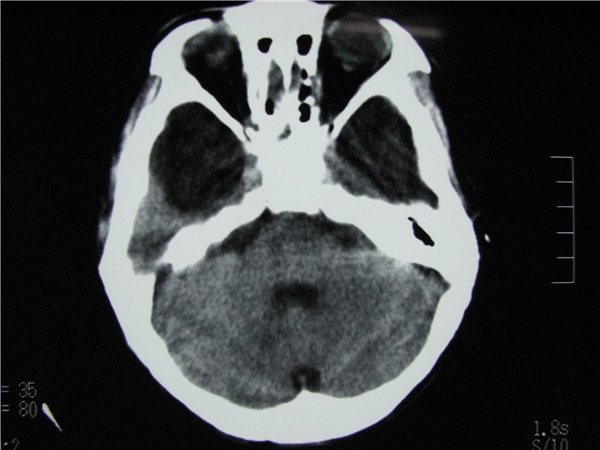

标题: CT20748:M 15Y 头痛,以前有外伤史请老师看看除了囊肿还有别 [打印本页]

标题: CT20748:M 15Y 头痛,以前有外伤史请老师看看除了囊肿还有别

m 15y 头痛,以前有外伤史请老师看看除了囊肿还有别的吗?

蛛网膜囊肿。眼拙,看不出别的,倒是看到了双侧大脑中动脉影,类似“致密动脉征”。

双侧侧裂池和纵裂池近前颅窝蛛网膜囊肿。

不能除外脑穿通畸形

无明显占位及负占位效应,考虑软化灶并脑室穿通畸形囊肿、局限性脑萎缩

蛛网膜囊肿,不能除外脑穿通畸形,支持。